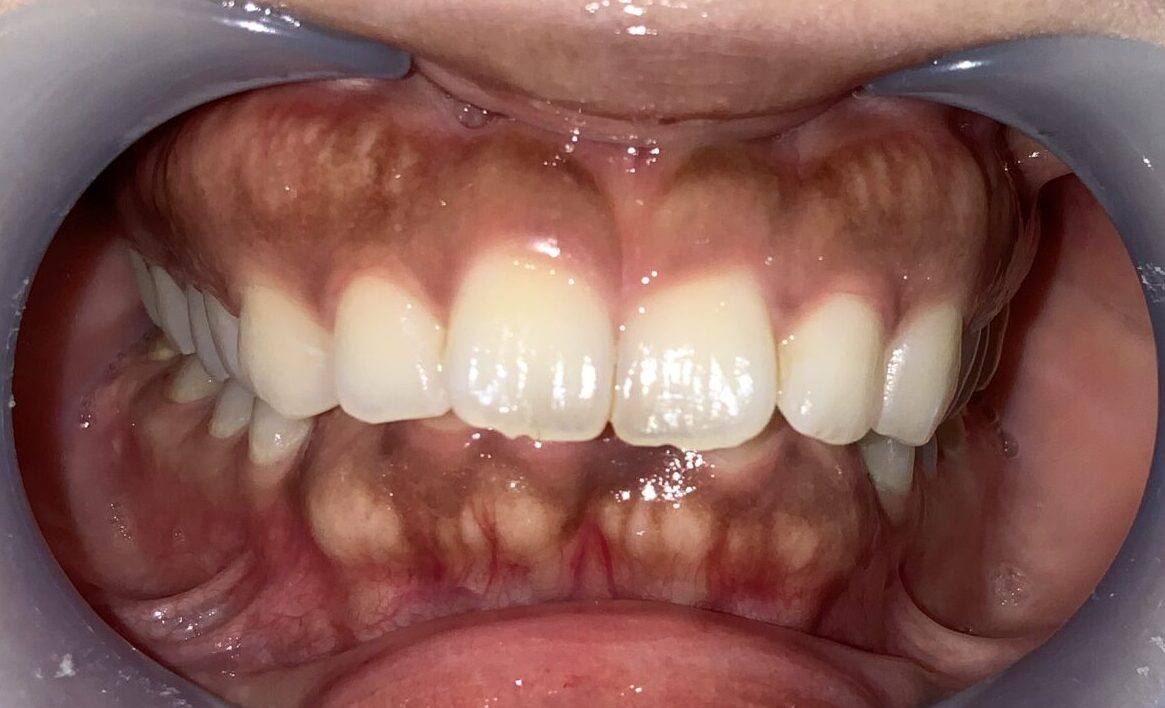

まずは手術前の状態です。

歯に歯ぐきがたくさんかぶっている状態です。

上の歯が下の歯を覆い被せてしまい、下の歯が全く見えない状態を過蓋咬合(かがいこうごう)と言います。

このような患者様は歯が歯ぐきに潜り込んでいる場合が多く、同時に歯槽骨が尖っていたり、ざらざらしていたり、歯槽骨までが歯を覆い被せていたりする場合がありますから、歯冠長延長術と同時に歯槽骨整形も一緒にしなければ、後戻りをしたり、綺麗に仕上がらない場合があります。